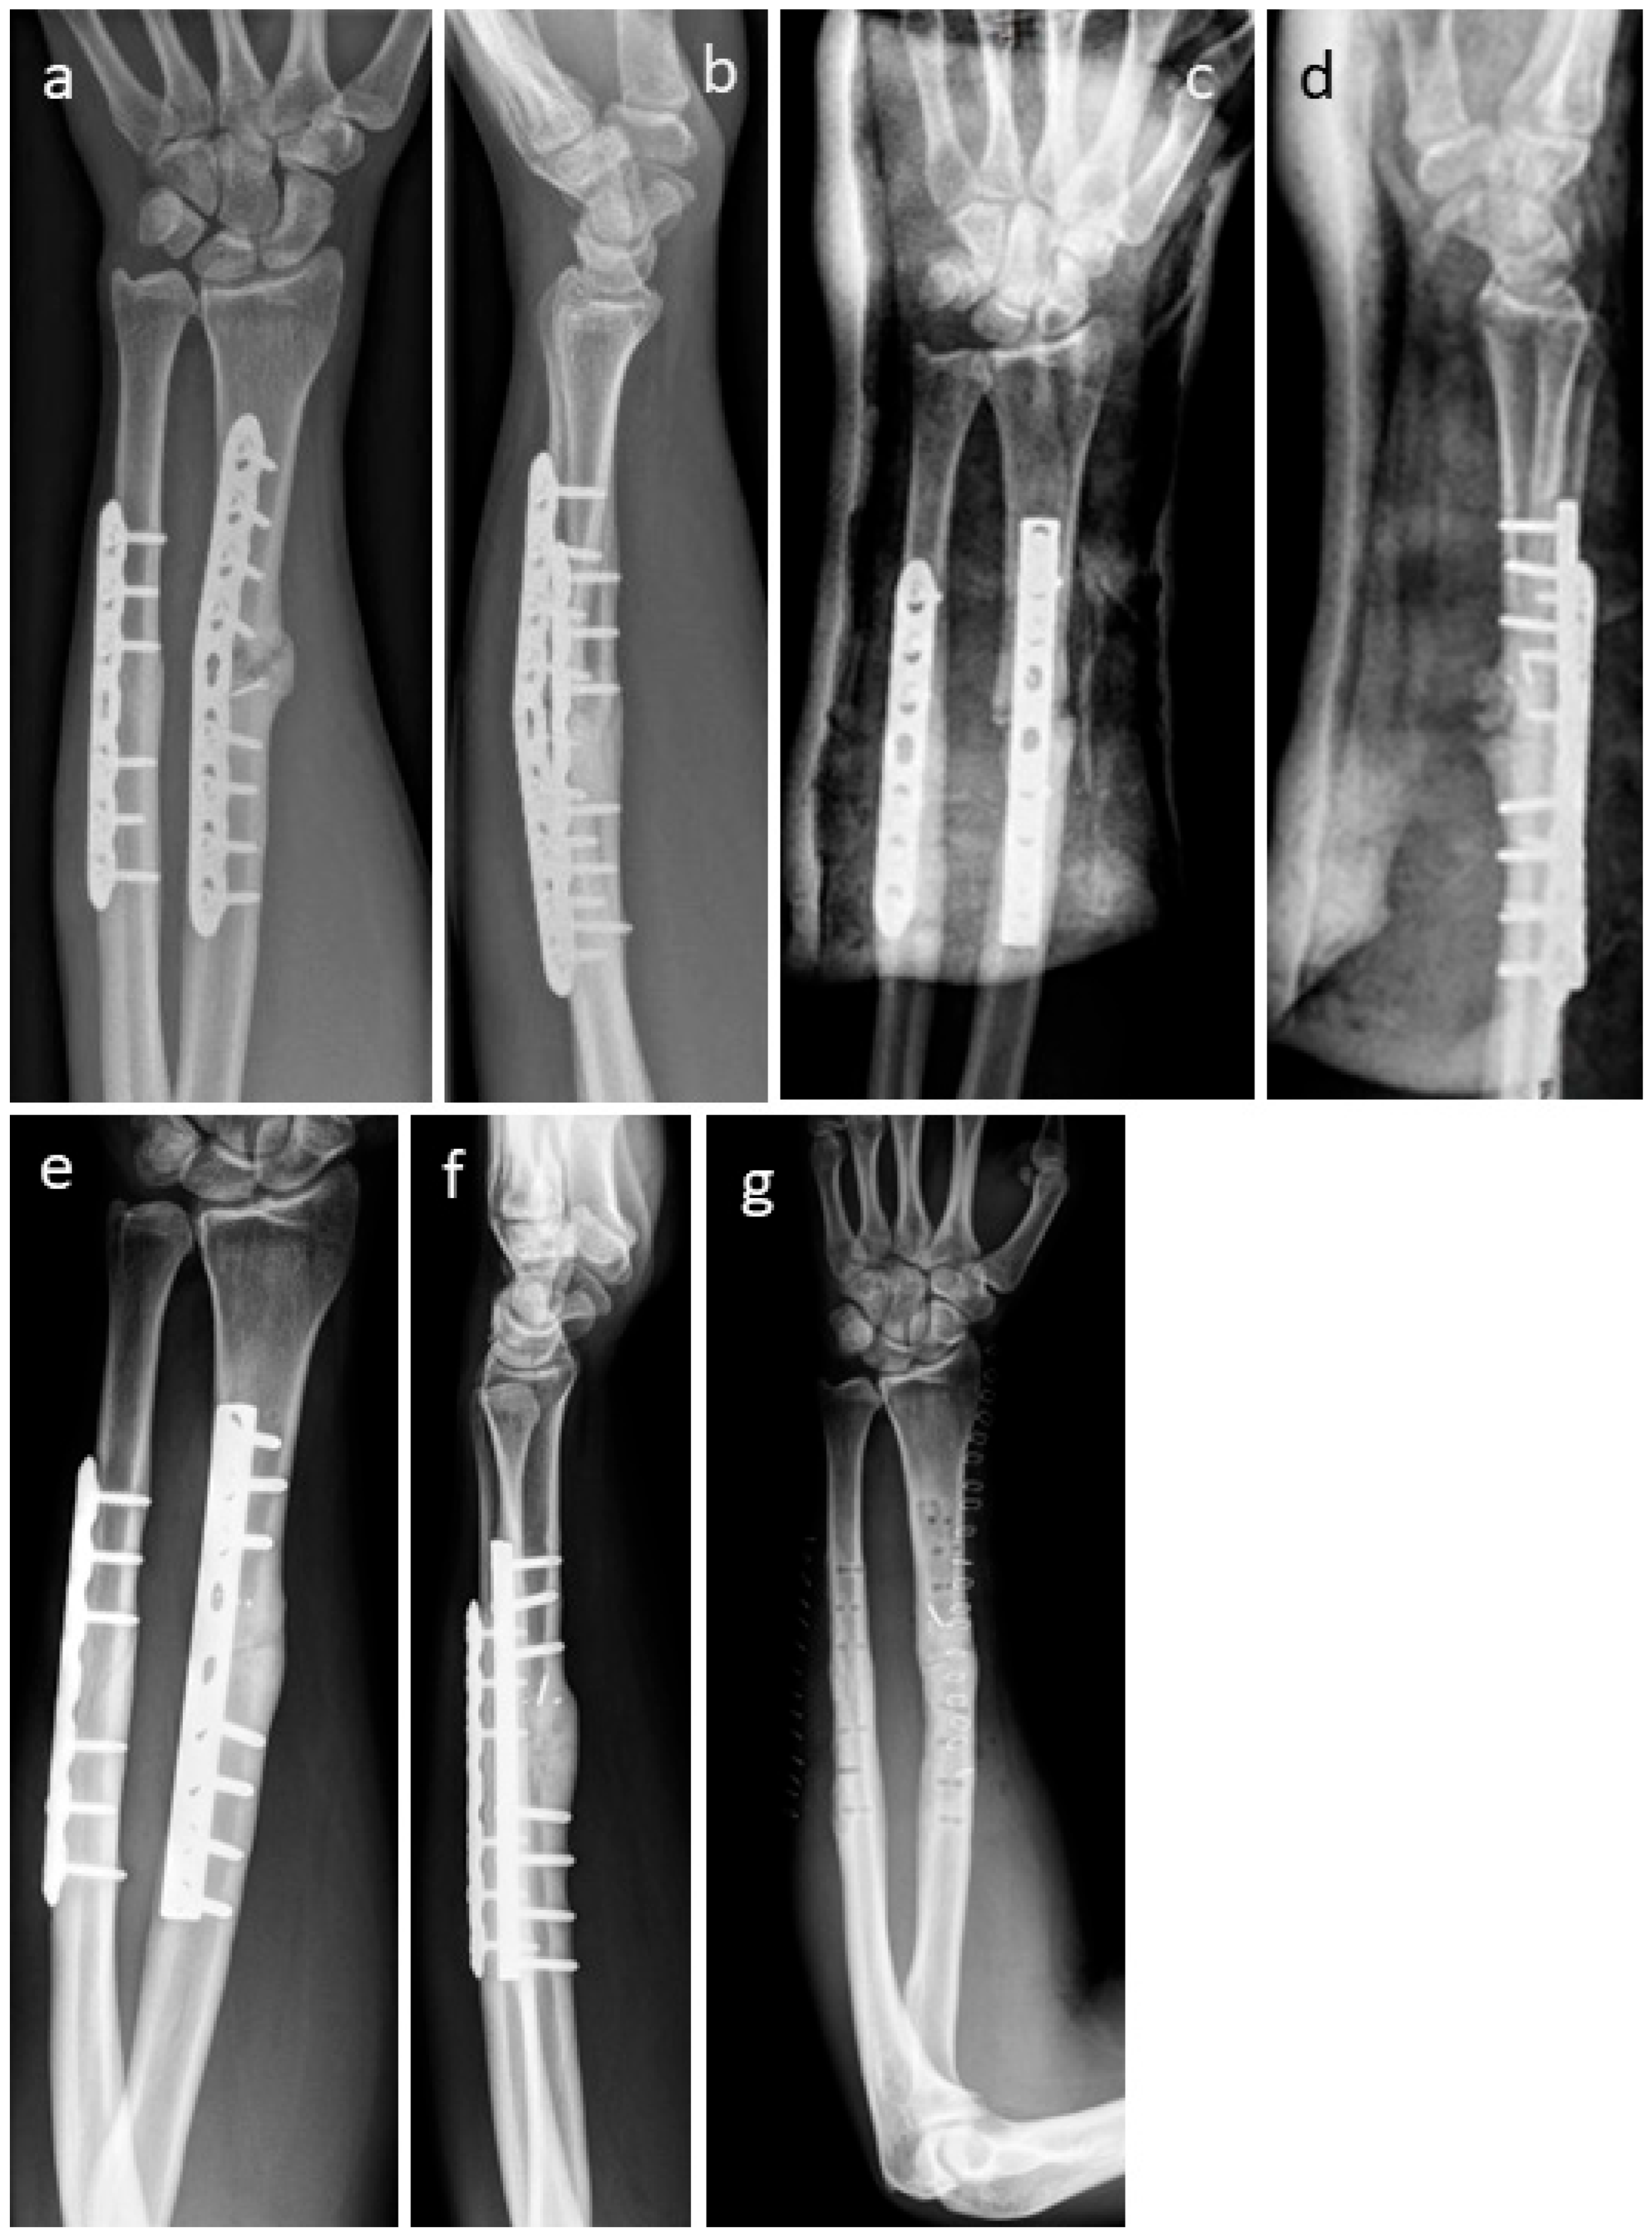

3.4. Selected Case Descriptions